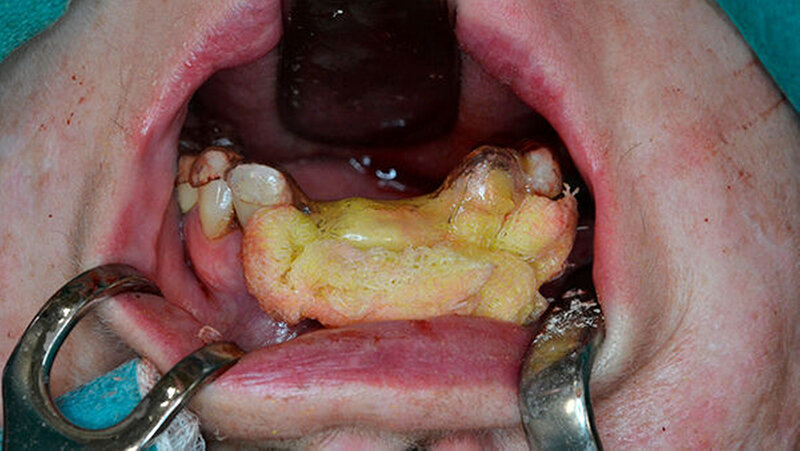

Nach erfolgter Tetrazyklinmarkierung mittels Doxycyclin 100 mg 1-0-0 für fünf Tage und präoperativer Abdrucknahme für eine Oberkieferverbandsplatte wurde der Eingriff in Intubationsnarkose durchgeführt. Nach marginaler Schnittführung wurden die Zähne 21, 12 und 13 entfernt sowie eine aufwendige modellierende Osteotomie im Sinne einer partiellen Resektion des Alveolarfortsatzes unter Schwartzlichtkontrolle in diesem Bereich durchgeführt (Abbildung 4).